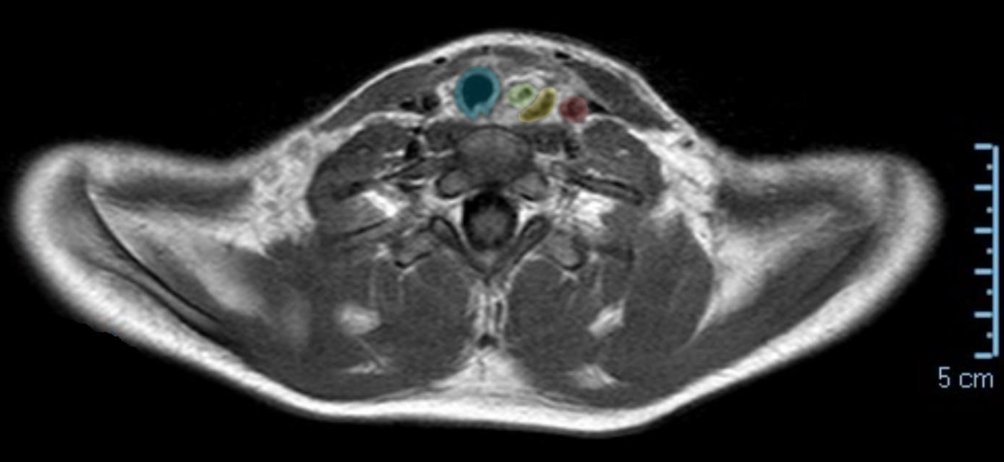

Die Extubation und Entfernung der Magensonde erfolgten bei klinisch und laborchemischem Normbefund bereits nach 12 h. In einem erneuten MRT am 2. postoperativen Tag war das Ödem des Ösophagus rückläufig und die operative eingebrachte Barriere zur ACC deutlich darstellbar (Abb. 2). Das Kleinkind konnte in uneingeschränktem Allgemeinzustand und nach vollständigem Kostaufbau am 3. postoperativen Tag nach Hause entlassen werden. Bei der geplanten Ösophagoskopie nach 2 Wochen waren lediglich 2 kleine narbige Areale zu sehen, welche sicher nicht obstruierend abheilen werden.

Abb. 2

Postoperatives MRT. Trachea (blau), Ösophagus (grün) deutlich weniger wandverdickt, zwischen Ösophagus und ACC (rot) das Kollagenflies (gelb)